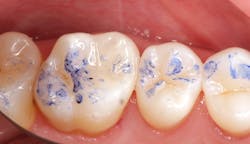

While performing esthetic dentistry, our bonding materials must work as promised to achieve long-term success.2 When manufacturers report bond strengths in the clinical arena, studies are conducted with the rubber dam in place (figures 1 and 2). When etched surfaces are exposed to the oral environment, including expired air while using typical isolation devices, the surfaces are challenged by moisture from numerous sources, causing the adhesive chemistry to be altered. Hence, to achieve the best bond strengths, a well-sealed barrier will help our results, often dramatically.